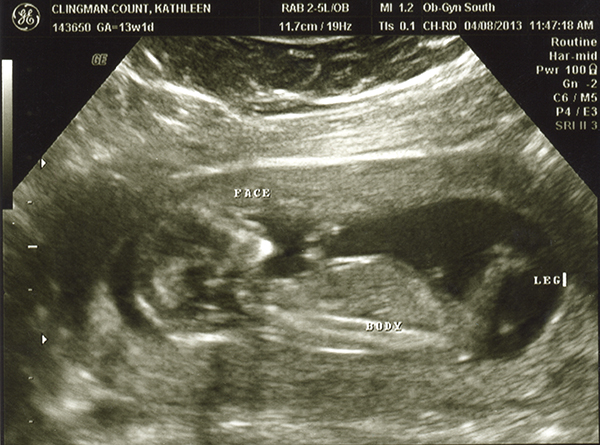

I had an ultrasound on Monday -- 13 weeks. I don't feel as though any of these are very clear pics. Even if they were better, I still wouldn't be any good with ultrasounds! Any of you experts able to make anything out with these? The tech guessed boy but the picture is not clear to me at all! She also kept saying the cord was between baby's legs and that we shouldn't go out and buy anything blue just yet. Any hope that it's a girl??

Attachment 10497

Very tough to tell. I don't see a nub in the profile shot and from what ladies say on here...13 weeks just isn't great for a potty shot to be accurate. I see why the tech guessed blue, but I think it could really go either way.